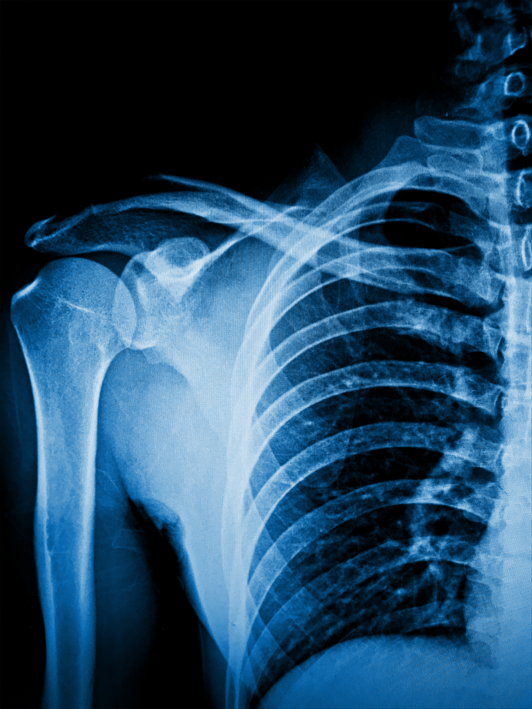

오십견

오십견은 어깨 관절의 염증으로 인해 통증과 운동 범위 제한이 발생하는 질환으로, 주로 중장년층에서 나타납니다.

오십견은 어깨 관절의 캡슐이 염증으로 인해 두꺼워지고 수축되어 어깨의 움직임이 제한되는 질환입니다. 일반적으로 중장년층에서 발생하며, 시간이 지남에 따라 통증과 운동 범위의 감소가 점진적으로 나타납니다.